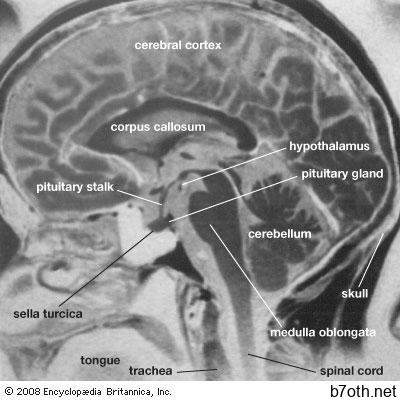

تقنيات الكمبيوتر المتقدمة جعلت من الممكن لعلماء الأشعة بناء الصور المجسمة التي توفر صورًا ثلاثية الأبعاد من المقاطع العرضية الرقمية التي حصلت عليها ماسحات التصوير بالرنين المغناطيسي التقليدية. هذه الصور المجسمة يمكن أن تكون مفيدة في تحديد موقع الآفات بدقة. التصوير بالرنين المغناطيسي له أهمية خاصة في تصوير الدماغ والحبل الشوكي وأعضاء الحوض مثل المثانة البولية والعظم الإسفنجي (أو الإسفنجي). يكشف مدى دقة الأورام بسرعة وحيوية ، ويوفر دليلًا مبكرًا على حدوث تلف محتمل من السكتة الدماغية ، مما يسمح للأطباء بإدارة العلاجات المناسبة مبكرًا. قام التصوير بالرنين المغناطيسي أيضًا باستبدال المفصل إلى حد كبير ، وحقن الصبغة في المفصل لتصور تلف الغضروف أو الرباط ، والنقي النخاعي ، وحقن الصبغة في القناة الشوكية لتصور الحبل الشوكي أو تشوهات القرص الفقرية.